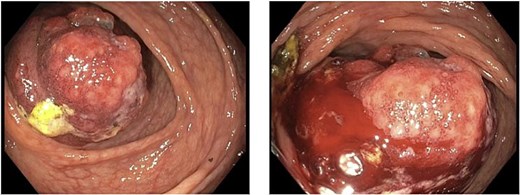

A 79-year-old Spanish-speaking male with hypertension, hyperlipidemia, and benign prostatic hyperplasia presented with intermittent, bilateral lower quadrant abdominal pain and nausea for 3 days. The pain was described as aching, non-radiating, and 6/10 in intensity. He had regular bowel movements and tolerated a normal diet. His past surgical history included a right inguinal hernia repair, and he had a normal colonoscopy 5 years prior, except for benign polyps. Lab work, including a carcinoembryonic antigen (CEA) test (0.5 ng/mL), was normal. A computerized tomography (CT) scan revealed a thickened cecum and ileocecal intussusception (Fig. 1). Gastroenterology performed a colonoscopy with cold forceps biopsies, revealing a large, infiltrative, polypoid mass in the cecum (Fig. 2). Pending pathology, the patient underwent a robotic-assisted right hemicolectomy due to impending bowel obstruction, followed by a functional end-to-end anastomosis. He tolerated the procedure well and was scheduled to begin chemotherapy with Bendamustine and Rituximab, selected due to his advanced age and frailty.

Colorectal MCL presents with nonspecific symptoms like abdominal pain, blood per rectum, fatigue, fevers, and weight loss [6, 7]. In this case, the patient only presented with abdominal pain and nausea. Given these nonspecific symptoms, diagnostic imaging is essential. CT scans help identify masses, lymphadenopathy, tumor size, and invasion depth. In this case, imaging revealed colonic intussusception, leading to surgical consultation. Similarly, Smith et al. [1] reported a case of MCL presenting with intermittent abdominal pain and colonic intussusception. Intussusception due to malignant lymphoma accounts for over 10% of colonic intussusceptions [3]. Colonoscopy and biopsy are key for visualization and diagnosis. In this case, CEA levels were normal, making it an unreliable marker for diagnosis [1, 6].